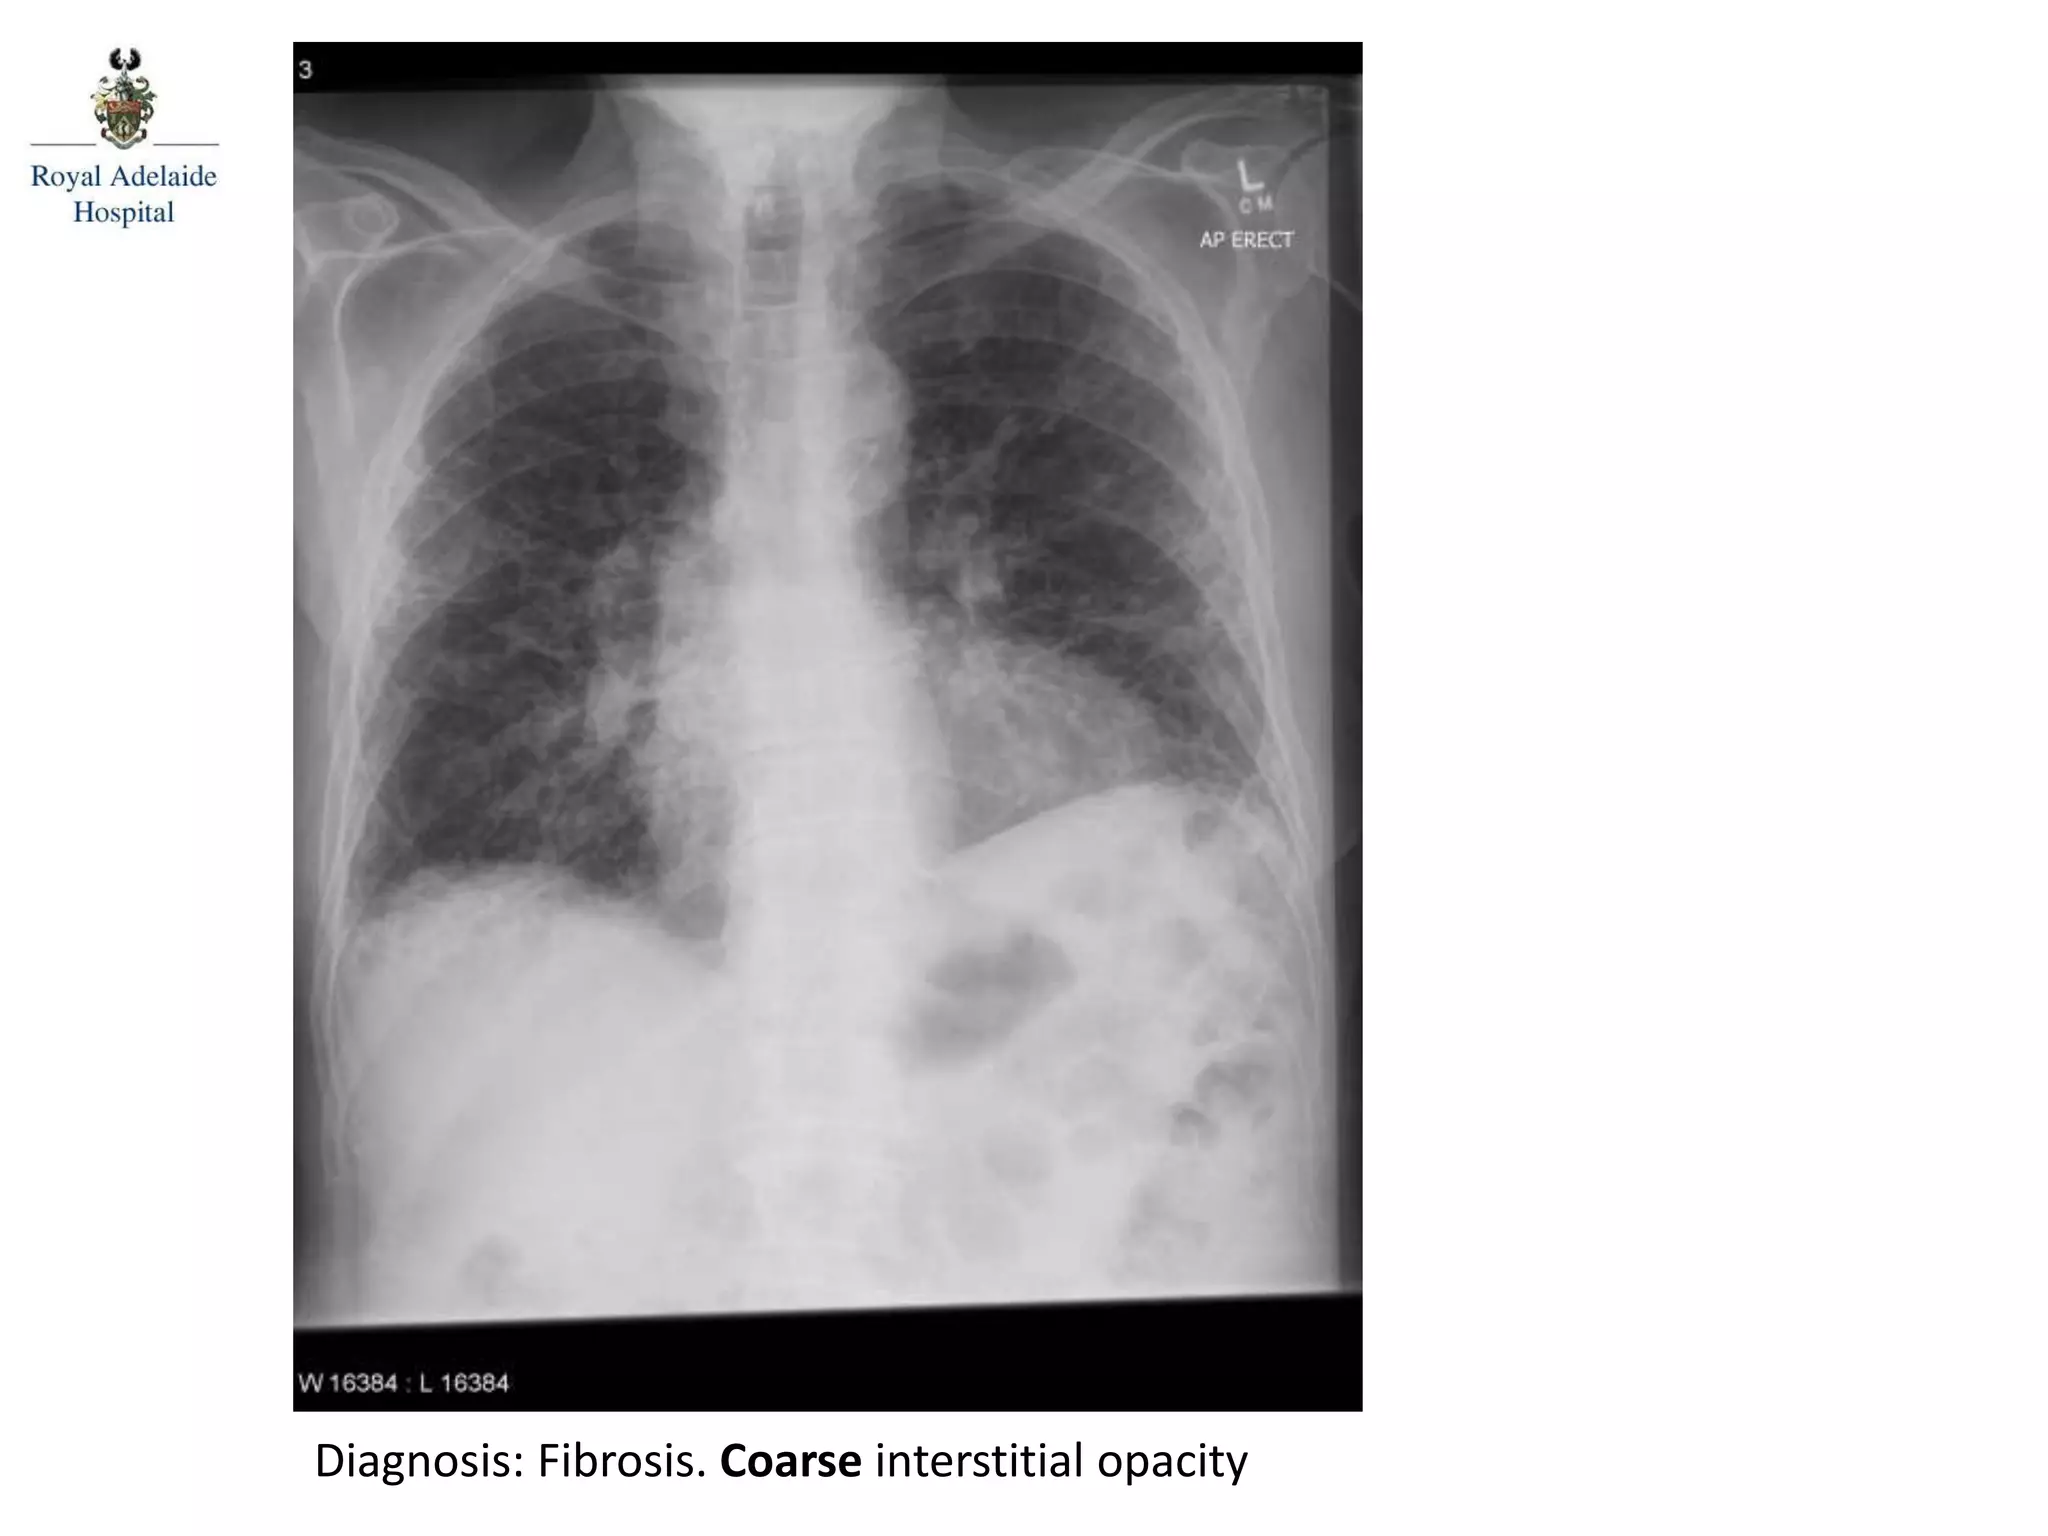

Diagnosis: Fibrosis. Coarse interstitial opacity